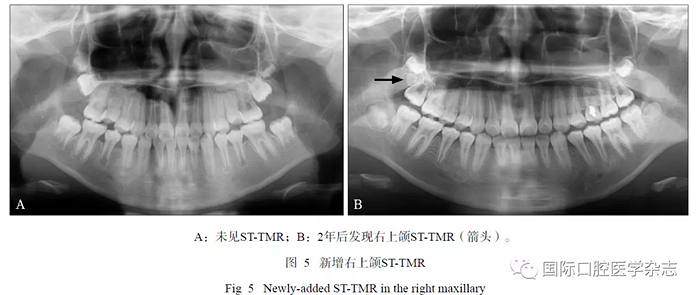

在17例有隨訪拍片的患者中,2例新增STTMR,其中1例患者第一、第二次拍片年齡分別為10歲、13歲(間隔2年7個月),另1例患者第一次、第二次拍片年齡分別為9歲、11歲(間隔2年,圖5);1例發(fā)生位置改變,ST-TMR由上頜第三磨牙方向近中移動(間隔2.5年,圖6)。

本研究對影像系統(tǒng)中的資料進行連續(xù)觀察,可觀察到ST-TMR的病例中最小年齡為11歲(3例),并分析對比2例追蹤發(fā)現(xiàn)新增ST-TMR的女性青少年患者前后2次拍片的年齡,推測上頜STTMR的出現(xiàn)可能約在10歲后,略晚于第三磨牙(8~11歲),這種影像表現(xiàn)的時間順序是否為普遍規(guī)律,仍需進一步觀察研究。